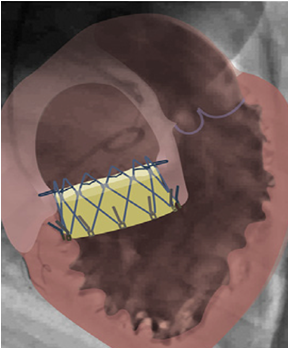

微创经导管三尖瓣置换手术

介入TV置换

图片

介入TV置换的临床试验

2018 TCT 国际多中心临床试验结果

✦ 例数:32例;年龄:73.5+12.9岁)

✦ 植入瓣膜大小:52mm(33%);48mm(25%);44mm(21%);40mm(17%);36mm(4%)

✦ 术中因位置不当中转外科手术:15.6%

✦ 术后30天:死亡率12.5%,ⅢAVB13.6%,RV穿孔 4.5%

✦ 超声:三尖瓣残余反流 —— 轻度11%;中度11%

LuX-Valve

✦ 植入人工瓣的大小不依据瓣环大小,而是依据有效瓣口面积,避免了人工瓣过大影响右室功能

✦ 植入人工瓣的固定不依靠瓣环

✦ 利用三尖瓣的瓣叶与人工瓣的裙边贴合、粘连,纠正瓣周漏